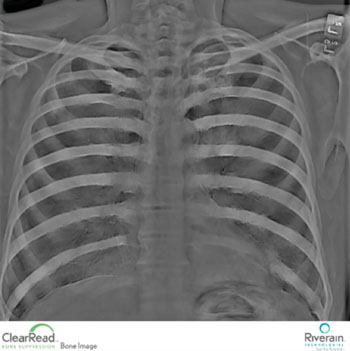

Clinicians are gathering important information from the most routine imaging exam, the chest X-ray, by using advanced software that enhances X-ray images captured by the equipment they already have or are in the process of buying. New bone suppression technology helps radiologists identify lung nodules and other serious medical conditions by converting a traditional chest X-ray into a soft tissue image without the ribs and clavicle bones. Posted on 19 Aug 2014

These structures typically obscure abnormalities. There are no further testing or radiation exposure for patients, and no need for imaging units or hardware for the hospital to buy or house to achieve the soft tissue image.

Image: An X-ray using the ClearRead bone suppression software technology (Photo courtesy of Riverain Technologies).